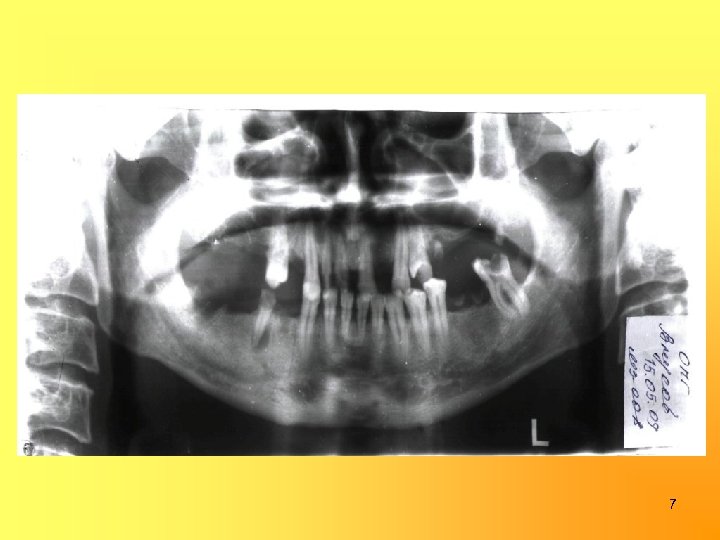

Зубная формула: II 0 0 R P I 0 I I P P P I II 0 P P R 0 0 R 18 17 16 15 14 13 12 11 21 22 23 24 25 26 27 28 48 47 46 45 44 43 42 41 31 32 33 34 35 36 37 38 R 0 0 Pt 0 C I II II I C I I R P 0 II 5

Вид прикуса: ортогнатический, глубокое резцовое перекрытие 6

7

ДИАГНОЗ: Хронический фиброзный периодонтит 16 (ИРОПЗ = 0, 8), 25 (ИРОПЗ = 0, 8), 28 (ИРОПЗ = 0, 7), 36 (ИРОПЗ = 0, 9), 48(ИРОПЗ= 0, 8); Хронический гранулематозный периодонтит 45 (ИРОПЗ=0, 7); Хронический фиброзный пульпит 15 (ИРОПЗ = 0, 5), 13, 12, 11, 23, 24, 37(ИРОПЗ = 0, 6); Средний кариес 34 (ИРОПЗ = 0, 2), 35 (ИРОПЗ = 0, 2); Частичная адентия в/ч и н/ч, 6 класс по Гаврилову (комбинированный); Генерализованный пародонтит средней степени тяжести, подвижность зубов II степени, потеря жевательной эффективности по Оксману = 66%. 11